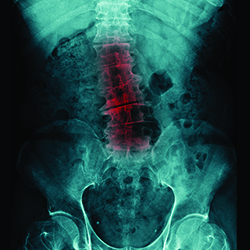

Scoliosis is an abnormal curvature of the spine that typically forms just prior to puberty. While most cases of scoliosis are so mild they do not necessitate treatment, there are cases of scoliosis that have been linked to conditions such as muscular dystrophy and cerebral palsy. If left untreated, scoliosis may also result in heart and lung problems. Luckily, this condition is treatable at MidAmerica’s Palos Hills and Mokena clinics.

Scoliosis is typically diagnosed through an analysis of one’s medical history, x-rays, and a physical exam. The physical exam generally requires the individual to lean forward with their arms dangling in order to note if one side of the rib cage protrudes more than the other.